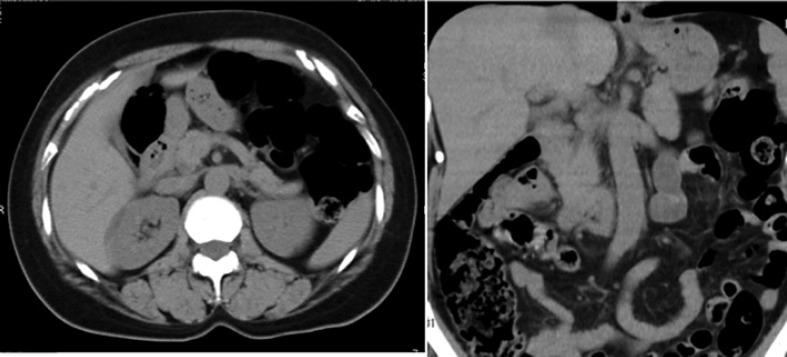

A 52-year-old woman visited our hospital with a complaint of upper abdominal pain. Abdominal computed tomography did not show any lesion responsible for the pain. However, esophagogastroduodenoscopy identified a pale, pink-colored, U-shaped foreign body stuck in the descending part of the duodenum. We removed it by gently pulling forward in an antegrade fashion with the use of a snare. Duodenography after the removal did not show any sign of leakage to the abdominal cavity or to the retroperitoneum. The foreign body was found to be a denture lining material equipped 3 days previously.

一名52岁女性因上腹部疼痛前来我院就诊。腹部计算机断层扫描未显示任何导致疼痛的病变。然而,食管胃十二指肠镜检查发现十二指肠降部有一个苍白、粉红色、U形异物嵌顿。我们使用圈套器以顺行方式轻轻向前牵拉将其取出。取出后十二指肠造影未显示有任何腹腔或腹膜后渗漏迹象。发现该异物为3天前佩戴的假牙衬里材料。